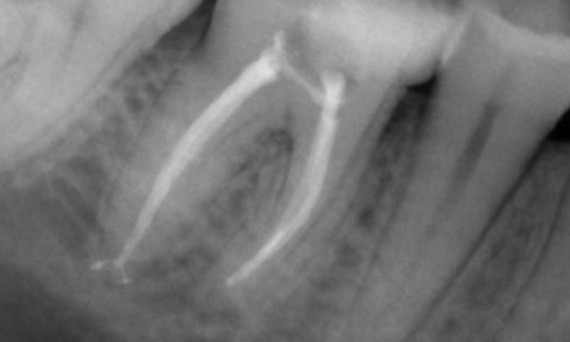

After: TruNatomy was chosen in this case to allow a caries leveraged approach and a focus on pericervical dentin preservation especially on the mesial aspect where the tooth had a more minimal restoration.